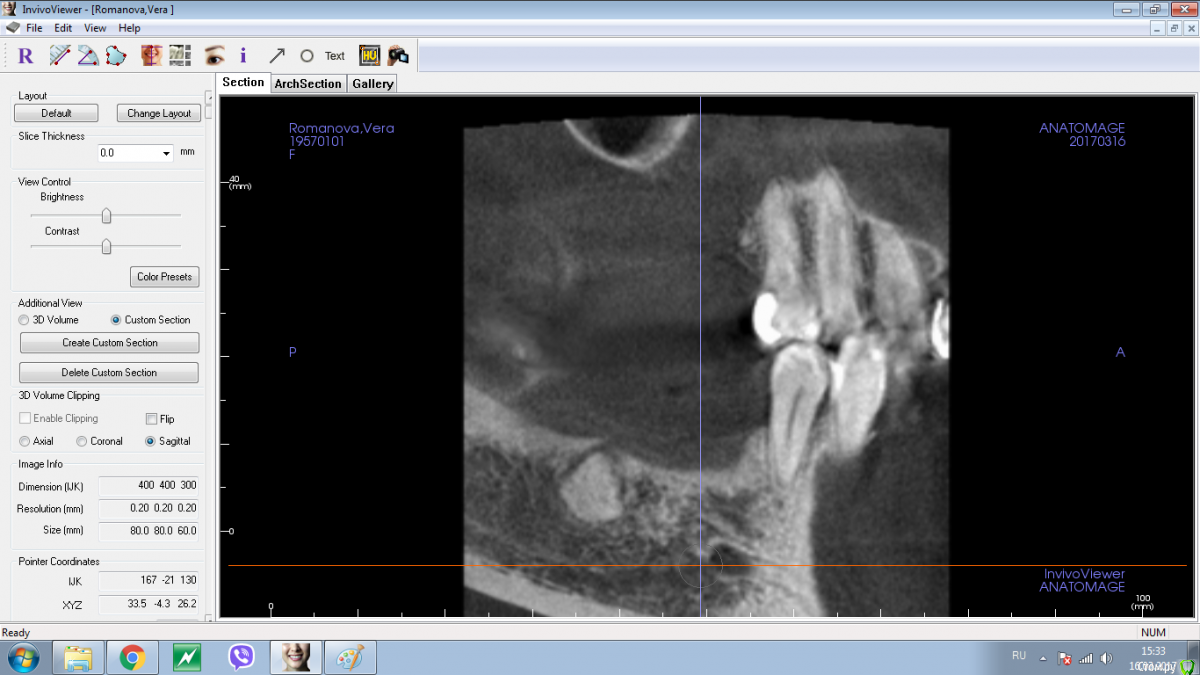

Shakirbura Опубликовано 18 марта, 2017 Поделиться Опубликовано 18 марта, 2017 Здравствуйте, коллеги!Пациентка обратилась по поводу протезирования на имплантатах. На снимке обнаружил вот такое образование. Раньше не встречал. Какими должны быть мои действия в таком случае?Спасибо! Ссылка на комментарий

Andrey Shiryaev Опубликовано 18 марта, 2017 Поделиться Опубликовано 18 марта, 2017 Похоже на остеому. Ссылка на комментарий

Kovalov Igor Опубликовано 19 марта, 2017 Поделиться Опубликовано 19 марта, 2017 Конденсирующая остеома.Покажите на Фейсбуке Рогацкину Дмитрию , читал что ставят прям в остеому Ссылка на комментарий

Карен Аванесов Опубликовано 19 марта, 2017 Поделиться Опубликовано 19 марта, 2017 Аккуратно убрать, поставить имплантат, при необходимости графт, если это остатки зуба будет видно. если нло на гистологию. Ссылка на комментарий